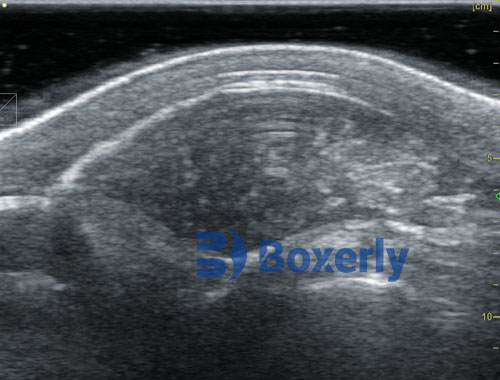

DZ20 measures pig back fat thickness and eye muscle area(1)

DZ20 measures pig back fat thickness and eye muscle area(2)